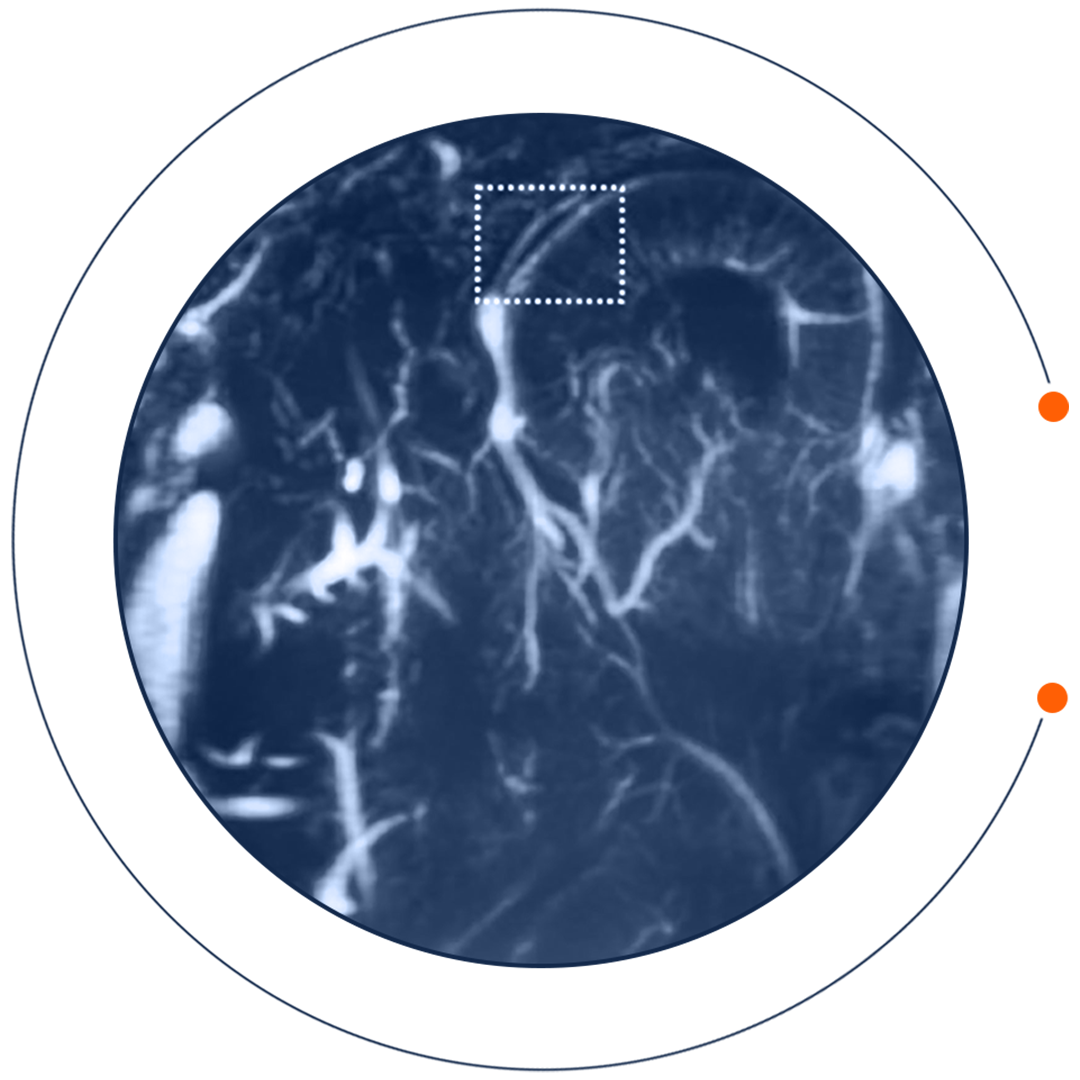

Boppart’s ARPA-H project, Margin Diagnostics (MarginDx), is developing a comprehensive high-resolution imaging system for detecting tumorous tissue during surgery. Combining advanced optical imaging technology with AI, it will discern whether tissue is tumorous in real time, helping surgeons remove as much of a tumor as possible. The goal is to significantly reduce the need for additional operations.

“For more than 15 years, my research group has collaborated with surgeons at Carle Health to develop and investigate uses for imaging technology in surgery,” he said. “This includes optical coherence tomography, revealing large-scale tumor structures without marks or dyes, and more recently nonlinear optics, in which small-scale structures respond to incident light by emitting distinctive light of their own. We integrated these components into a single device, where the response of one laser pulse gives all this information at once.”

The system will then use AI to identify signs of cancer.